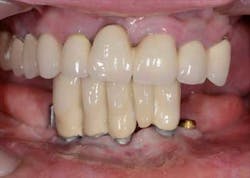

Fig. 2: Remaining teeth in the upper right

Mandibular arch: the lower jaw is fully edentulous. Initially, according to the patient, an implant-supported five-unit bridge (23 to 27) was made on four implants (Alphabio®) placed in 2007. Tooth 22 was present at the time and a removable partial denture replaced the bilateral posterior missing teeth.

Then, in January 2012, tooth 22 was extracted and a second implant specialist placed a new implant (Zimmer Dental®) to replace it. The GP decided to use a Locator® attachment system on this new implant and have the existing denture stabilized over it, without paying any attention to the collapsing situation of the upper right.Fig. 3: CT scan shows the existing implants positions and the bone volume available